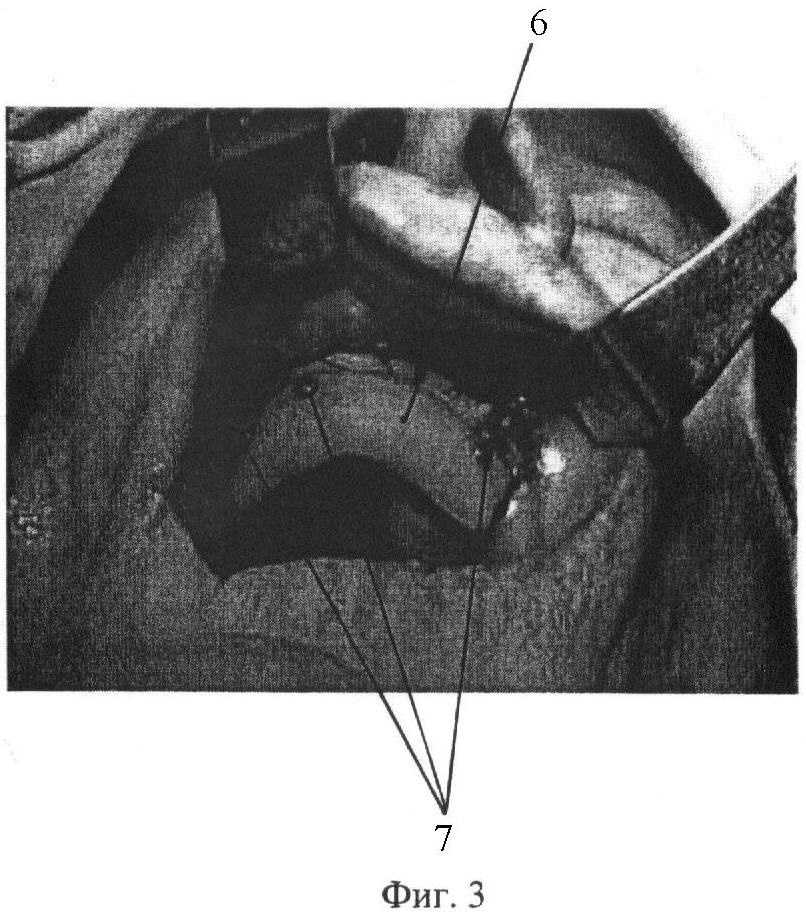

На фиг. 1-3 представлены этапы выполнения способа.

До операции в зуботехнической лаборатории по гипсовой модели 1 челюсти больного (фиг.1), на которой путем гравирования материала в области прикрепления подвижной слизистой оболочки 2 создают высоту 3 ската альвеолярной части, необходимую для фиксации съемного протеза. На полученной модели маркируют границы 4 необходимого кожного трансплантата и в заданных границах 4 формируют восковую модель 5 базиса пластмассового пластиночного протеза (фиг.2), которую традиционным способом заменяют на акриловый пластмассовый пластиночный аппарат. По размерам базиса пластиночного аппарата у больного под местной анестезией забирают кожный тонкий трансплантат, например, с внутренней поверхности плеча и фиксируют швами в раневую поверхность альвеолярной части челюсти, а акриловую пластину 6 укладывают на кожный трансплантат и фиксируют стальными шурупами 7 к компактной пластинке челюсти (фиг.3).

Больной М., история болезни 3312, поступил 08.02.2007 г. на лечение по поводу папилломатоза и выраженной атрофии альвеолярной части переднего отдела верхней челюсти при полном отсутствии зубов. Ввиду сложной клинической картины больному ранее было отказано в ортопедическом лечении. Получена гипсовая модель верхней челюсти, на которой путем гравирования в области прикрепления подвижной слизистой создана высота ската альвеолярной части в переднем отделе, необходимая для фиксации съемного протеза, на модели отмечены границы будущего фиксирующего устройства кожного трансплантата (фиг.1). По отмеченным границам изготовлен пластмассовый пластиночный аппарат (фиг.2). Под местной анестезией удалена папилломатозно измененная слизистая оболочка переднего отдела верхней челюсти, на внутренней поверхности плеча по размерам базиса пластмассового аппарата (фиксирующего устройства) взят тонкий кожный лоскут, который перенесен в дефект слизистой оболочки переднего отдела верхней челюсти и ушит. На кожный перемещенный лоскут помещен пластмассовый акриловый пластиночный аппарат, повторяющий размеры кожного трансплантата, и для достижения плотного прилегания фиксирован стальными шурупами к компактной пластинке верхней челюсти (фиг.3). Послеоперационное течение без осложнений. Назначались антибактериальные препараты в среднетерапевтических дозах, проводилась гипосенсибилизирующая терапия. Больной выписан из клиники на шестые сутки. Через 3 недели амбулаторно удалено устройство, фиксирующее кожный трансплантат, заживление первичным натяжением. Созданы благоприятные анатомические условия для протезирования. Больному наложены полные съемные протезы. На контрольных осмотрах через 3 и 6 месяцев больной жалоб не предъявлял, отмечая хорошие эстетические и функциональные качества протеза.